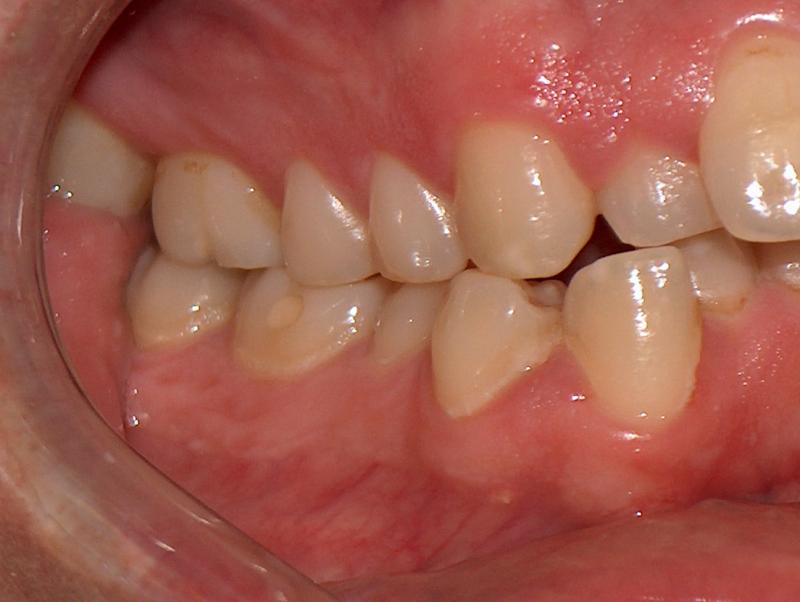

Steve N.

Invisalign Case

INVISALIGN, 16 months, 2 series of aligner to correct the anterior cross bite, to intrude the over erupted and extremely crowded lower incisors. COSMETIC DENTISTRY, leveling of incisal edges, gingival tissue contouring, and cosmetic bonding.

Cosmetic Dentistry, Mid-line Asymetry, Severe Crowding